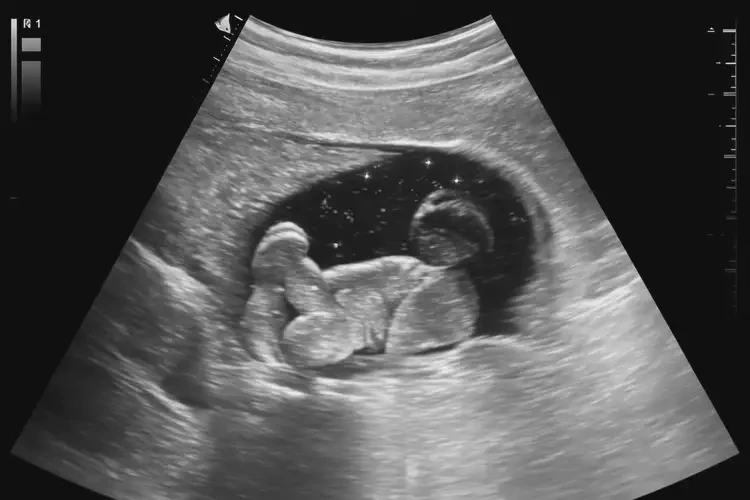

懷孕第10周胎心90寶寶還能要嗎(圖2)